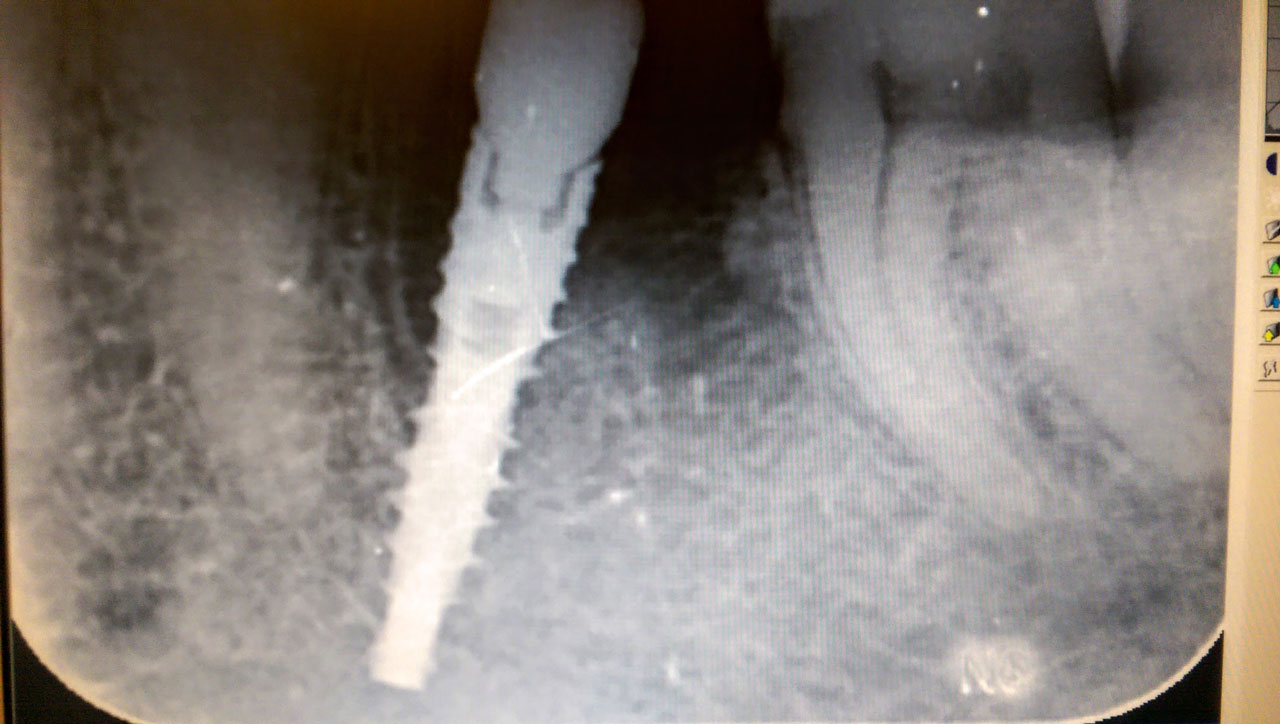

Implantátum és cirkónium korona

Harapás helyreállítása asztétikus cirkónium koronákkal

Rágófunkció esztétikus helyreállítása azonnalterhelhető svájci IHDE implantátumokkal és porcelán koronákkal.

A régóta fennálló foghiány és a mozgó fogak miatt a páciens nem tudott jól rágni és harapni, illetve mosolyogni sem mert már jó ideje. A leggyorsabb és a legesztétikusabb megoldás az ilyen esetekre az IHDE azonnal terhelhető implantátumok behelyezése, és az azokra rögtön elkészített porcelán koronák elkészítése.

A teljes munka - az implantáció, a végleges koronák elkészítése - 5 munkanapot vett igénybe.